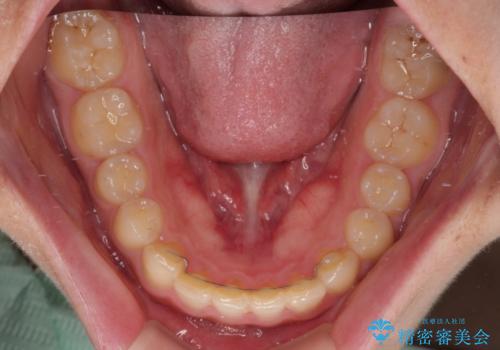

正面や横からの写真ではきれいに治っており、患者様は大変満足のいく仕上がりとなりましたが、深い咬み合わせの改善は不十分で、奥歯の咬み合わせも改善させることができませんでした。

インビザラインは、咬合力の強い方ですと、奥歯が歯肉内にめり込んでしまうため、前歯が強く接触してしまうことがあります。

こちらの方は、奥歯はしっかりと噛んだのですが、歯肉にめり込んでしまったことで、歯肉が腫れやすくなってしまいました。